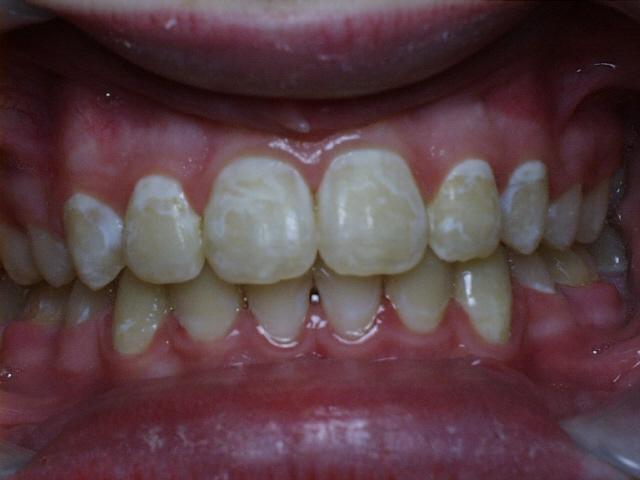

Moderate crowding with crossbites of the front teeth.  Treatment time was 24 months.  No permanent teeth were extracted in this case, but two deciduous cuspids seen in the initial photo were extracted after the braces were placed.  The molars were class 3 (lower molars too far forward at the start of treatment).